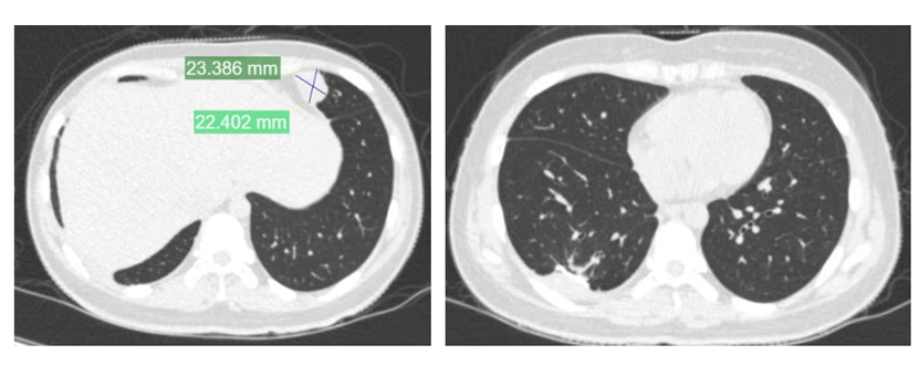

夏夏前期接受了术前化疗、截肢手术及术后化疗,使用的是一线化疗方案。然而,结疗不到一年,肺部出现转移病灶,经过手术切除后未再进行化疗。术后5个月,左肺再次发现新发转移病灶。

2024年11月,夏夏接受胸腔镜下右肺下叶切除术。2025年1月复查:右肺术后改变。

夏夏在最新的视频中表示,癌症转移到胸膜,她去瑞金医院寻求治疗方案,她将在上海接受肋骨和胸膜的切除手术。视频中的夏夏虽然有疲态,但依旧乐观,还感谢帮助她推轮椅的好心人。